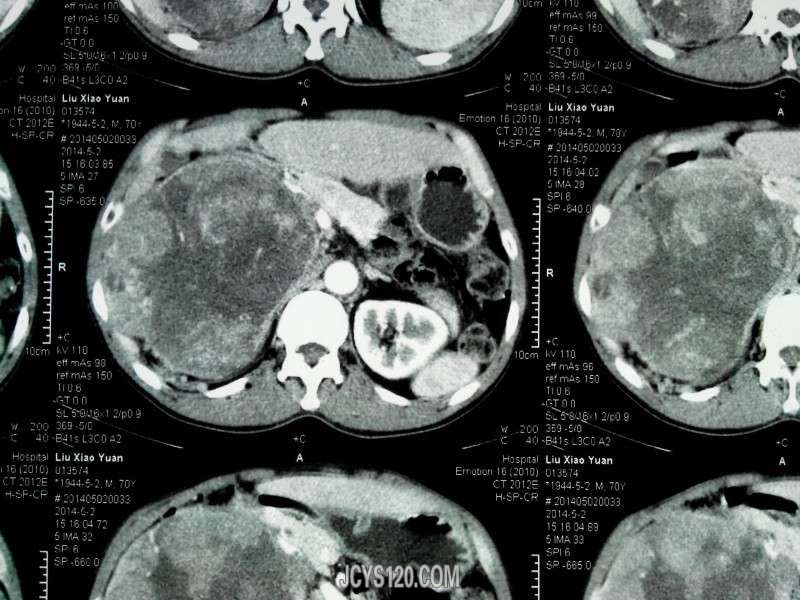

患者女性,70岁,体检发现,大家诊断什么病,怎么治疗。谢谢!